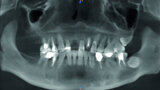

Fig. 3: Pre-op panoramic radiograph.